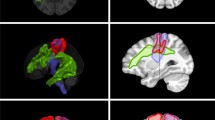

Firstly, the cortical surface and tractography of existing fiber bundles, based on commonly used clinical software, and delineation of other relevant regions of interest, such as a tumor to be resected, are required. The MRI sequences which were used for the DTI FT were performed on 3 T magnetic resonance scanners (Philips Medical System, Netherlands B.V.). All patients obtained MRIs according to the standard glioma protocol at our department including a T1-weighted three-dimensional (3-D) gradient echo sequence with intravenous contrast administration for anatomical co-registration, a T2-weighted 3-D FLAIR sequence, and DTI sequences with 32 orthogonal sequences. For the visualization of white matter pathways, we performed DTI FT of eloquent pathways such as the corticospinal tract (CST), the arcuate fasciculus (AF), the inferior and middle fronto-occipital fasciculus (IFOF, MFOF), the frontal aslant tract (FAT), and the superior and inferior longitudinal fasciculus (SLF, ILF). Therefore, we used our standard deterministic algorithm with a fiber assignment by continuous tracking (FACT) (iPlan® Net Cranial 3.0.1 and Brainlab Elements, Brainlab AG, Munich, Germany). The regions of interest (ROI) were chosen based upon anatomy and function. The latter ROIs were based on preoperative navigated transcranial magnetic stimulation mappings (nTMS) [12]. Figure 1 shows the 3-D reconstructions and the visualized steps of the prepared cases.

The figure shows the 3-D reconstructions of the prepared cases 1–5 (rows) as summarized in Table 1. Per row this figure shows the step by step reduction of anatomy until specific function-related fiber tracts are revealed. Case 1: a cerebral cortex and transparent skin including tumor and ventricles; b whole brain tractography; c specific fibers revealed, such as CST (yellow), FAT (blue), IFOF (green), and AF (pink). Case 2: d cerebral cortex and skin including tumor and ventricles; e cerebral cortex and transparent skin; f whole brain tractography; g IFOF (green), tumor, and ventricles; h SLF (pink), tumor, and ventricles. Case 3: i cerebral cortex and transparent skin including tumor and ventricles; j whole brain tractography; k specific fibers revealed for motor and language, such as CST (yellow) and SLF (pink). Case 4: l cerebral cortex and skin including tumor and ventricles; m whole brain tractography; n whole brain tractography without head; o specific language (pink) and motor (yellow)-related fibers revealed. Case 5: p whole brain tractography and skin including tumor and ventricles; q additional cortical location of motor (green) and language (pink) function; r specific fibers revealed, such as CST (yellow), FAT (blue), IFOF (green), SLF (pink), optic radiation (red), and tumor; s the skin, tumor, and ventricles plus MEP-positive sites of cortical motor function (green) with CST (yellow)

A 3-D model of the chosen objects can be added into the AR display (Figs. 2 and 3). The pre-selected cases were presented chronologically (Fig. 1). The participants were divided into subgroups of five. Each participant was equipped with an AR goggle headset. In each subgroup of five, one was designated as “master.” The master was equipped with a controller which allowed them to zoom and rotate the model. They were also able to perform virtual dissection of the fiber tracts by peeling away additional layers. In additional, the master’s view was presented via live screen for review by the remainder of the group who were not wearing goggles for that particular session. Figures 2 and 3 show screenshots of the participant view during the application of AR for fiber dissection. Figure 1 shows the step-by-step neuroanatomy dissection revealing function-related fiber tracts.

The figure shows a screenshot visualizing the participant view during the application of AR for fiber dissection. The 3-D reconstruction is shown from left occipital. The green and red laser pointers can be used to describe structures or answer questions between participants or moderator. Additionally, the patient’s 2-D MRI scan slices can be visualized in the background and can be scrolled

Participants recommended that, for future applications, more anatomical structures should be included in the simulation to improve orientation. In fact, this is already available but was not offered as an option for this simulation assessment. The anatomical reconstructions used included pre-selected language pathways, the 3-D reconstruction of the tumor, and the modeling of the patients’ skin (Fig. 1). We also included a reconstruction of the cortex to evaluate this additional request (Fig. 1).